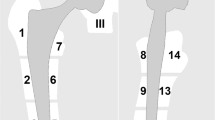

The artifact area varied with the different types of prostheses as well as the material of the prosthesis components (Figs. 5 and 6). In the MoM prosthesis, the artifact area in the T1 VAT + SEMAC sequence was similar to that in the T1-hiBW sequence. Despite the better delineation of the MoM implant with SEMAC, it does, however, show an additional area of signal void adjacent to the cranial aspect of the acetabular component (Fig. 7), which is why the total artifact area is not improved compared to the VAT sequence without SEMAC. The STIR-mRFp showed significantly less arifact area compared to the STIR-hiBW (Fig. 8). The descriptive statistics of the artifact area are listed in Table 5.

Artifacts in the T1 VAT images of (a) an MoM prosthesis with large artifacts in the cup region with low signal (*) and pile-up effect (arrowhead) in the femoral region and distortion (arrow), (b) a prosthesis with a cemented metal cup with a polyethylene lining and cemented stainless steel stem with a large artifact in the cup and stem region but less distortion since the lining is not metal and (c) a prosthesis with a cemented cup with non-MoM and uncemented titanium steel showing fewer artifacts in the cup and stem region

Regarding the artifacts in the prostheses groups in our study, there was more distortion in the MoM prosthesis group, but artifact areas were overall larger in the non-MoM prosthesis group, with wide ranges of the measurement of distortion and artifact area in both groups. These variations were caused by the difference in material in the prosthesis components between and within the groups. The acetabular component of the MoM prostheses consisted of a cobalt-chromium alloy and of the non-MoM of a polyethylene liner. The stem in MoM prostheses varied from a short cobalt-chromium alloy base in the surface replacements to a long titanium stem in non-surface replacement prostheses. In the non-MoM prosthesis, the stem was of stainless steel or titanium. Since we compared the sequences in the same patients, the differences of the prosthesis parts did not affect the results.